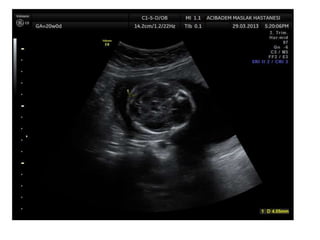

1st trimester

Increased nuchal translucency

2nd trimester

Multiple major anomalies

Single major anomaly + Trisomy 18 marker

Choroid plexus cyst + other anomalies

Early IUGR